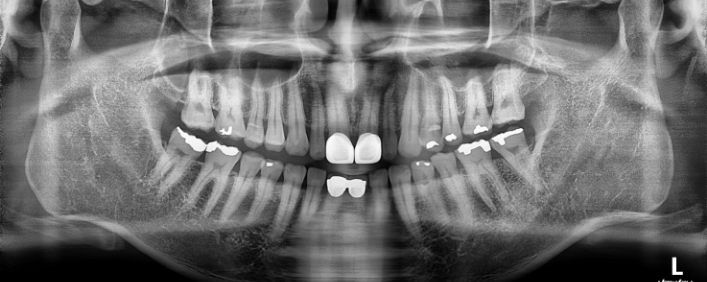

박** 환자분 (오른쪽 상하악 사랑니 동시 발치 케이스)

상악의 경우 단순매복으로 발치 및 동시에 하악 잇몸뼈에

깊게 박혀잇는 고난이도 케이스, 잇몸절개 후 치아 분리하여

발치하였으며